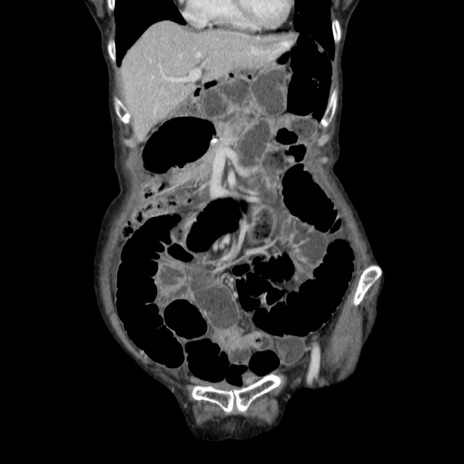

横断像